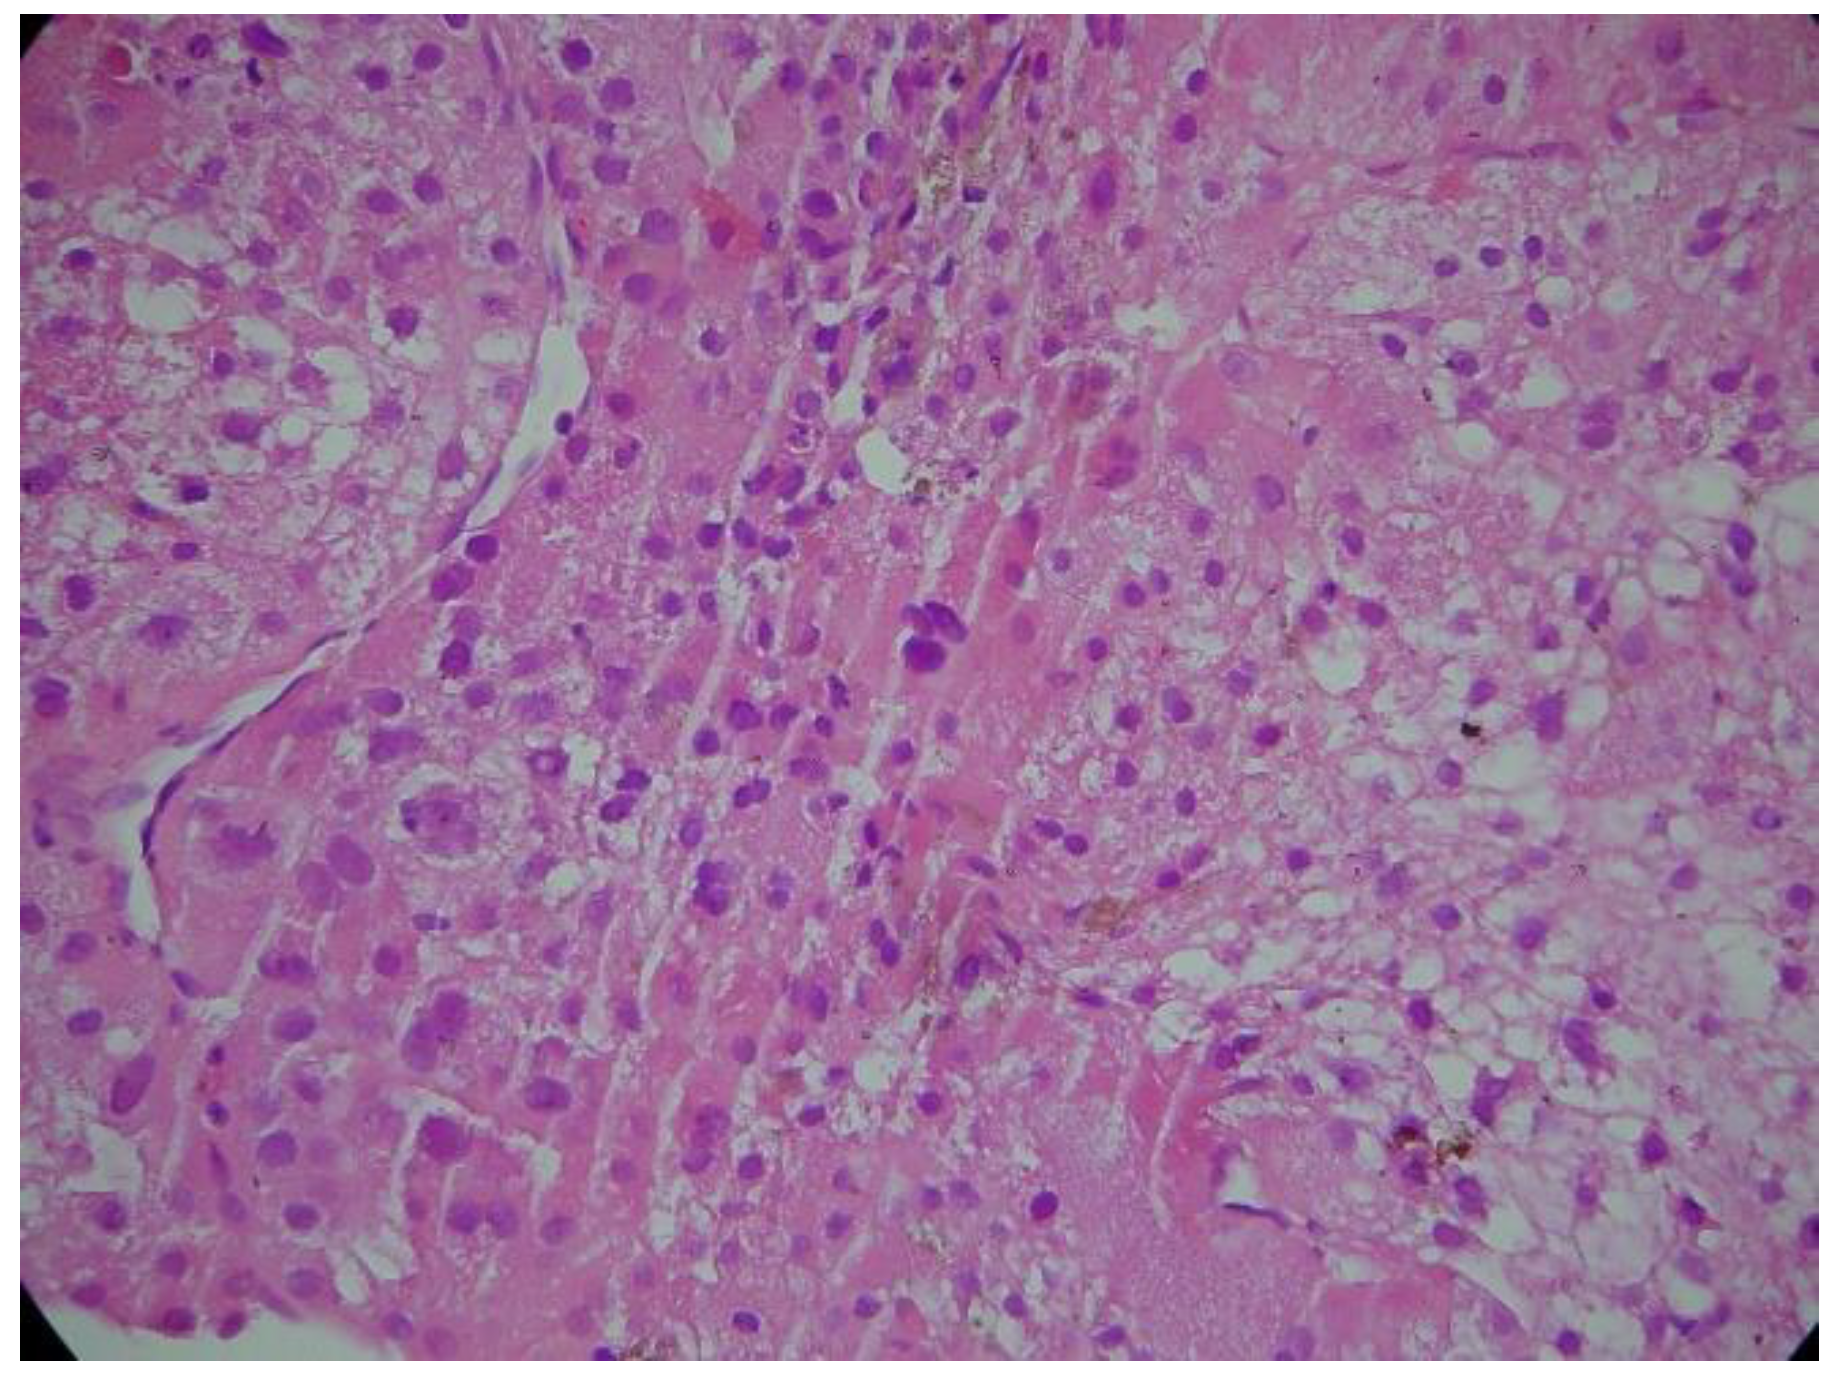

Case report